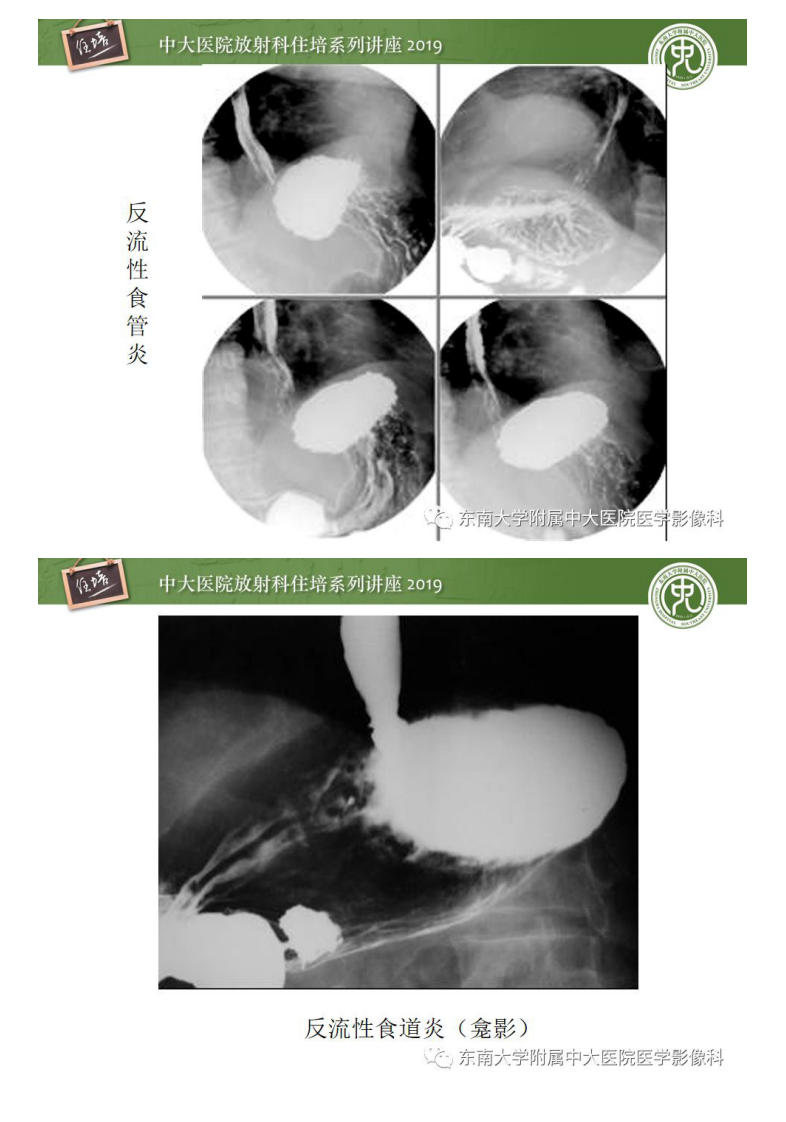

20190616_1【中大放射住培系列讲座第65期】食管常见疾病的诊断和鉴别诊断.pdf